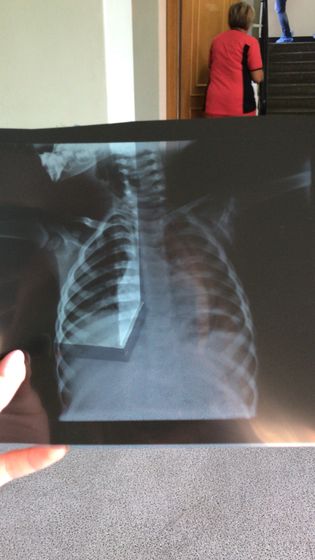

Выписали нас из больницы с диагнозом Фото прилагаюИнфекции нам не подтвердили Сегодня врач пульмонолог аллерголог к которой мы пошли по причине кашля, который не проходит, наругала меня за то, что нас выписали из больницы и прокапали антибиотиком всего 4 дня. На дом назначили супракс и полиоксидоний в нос капать. А положили нас в больницу с кашлем,39,6 и подозрением на мононуклеоз с опровергли и сказали. Лечитесь дома, кашель пройдёт. Но он как был так и естьНе нон стоп, но есть. А, ещё сказали дома дышать противоотечной смесью. Пульмонолог тоже слушала, сказала чисто, отправила на рентген, там тоже всё чисто, отправила к лор -там всё чисто. Но